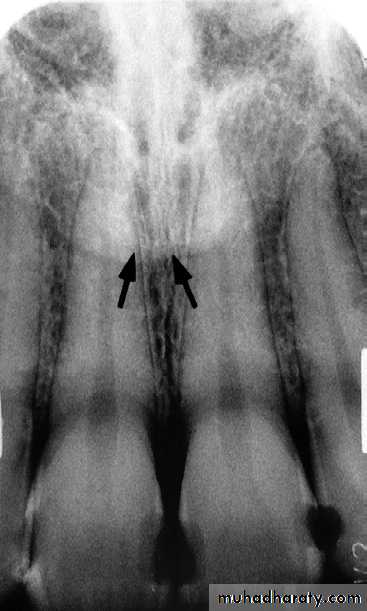

NUTRIENT CANALS

:

Nutrient canals carry a neurovascular bundle and appear as radiolucent lines of fairly uniform width. They are most often seen on mandibular periapical radiographs running vertically from the inferior dental canal directly to the apex of a tooth or into the inter dental space between the mandibular incisors.